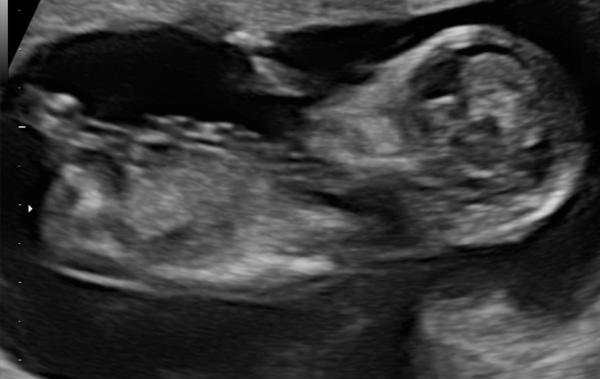

Huhu, wer mag kann ja gern mal schauen ob man schon erkennen kann welches Geschlecht es wird. Es gibt da ja verschiedene Theorien. BIn einfach zu ungeduldig und gespannt:)